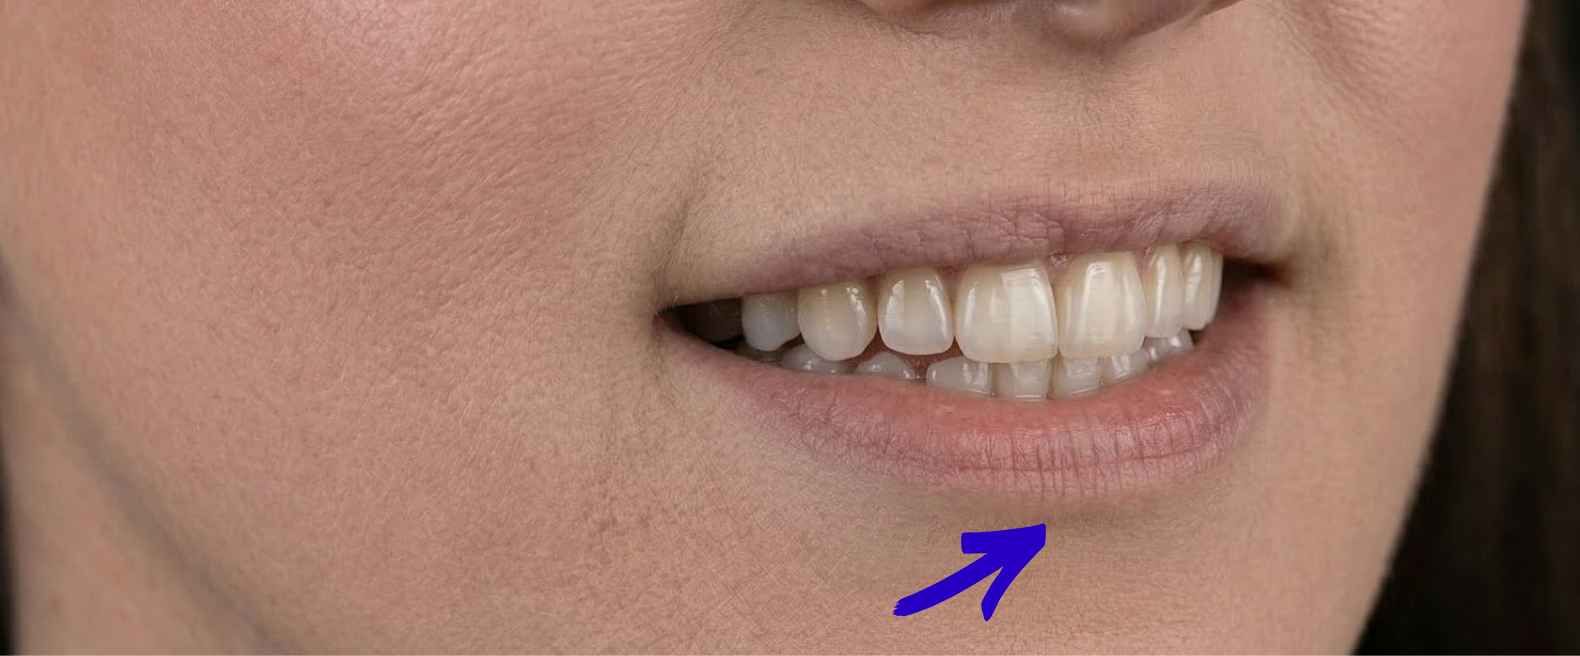

Cofnięcie się do punktu wyjścia

Pierwszy odruch w takiej sytuacji jest dość oczywisty - szukamy miejsca do korekty. Tylko że tutaj rozwiązanie było dużo prostsze. Wystarczyło wrócić do zdjęć sprzed zabiegu. Dopiero wtedy było widać, że:

- to wgłobienie było obecne już wcześniej

- po zabiegu nie powstało nic nowego

- zmieniła się jedynie jego widoczność

Źródło: zdjęcie własne. Usta pacjentki przed zabiegiem.

Źródło: zdjęcie własne. Usta pacjentki przed zabiegiem.

Co tak naprawdę się tutaj wydarzyło?

No dobra, to co właściwie się tu wydarzyło? Kwas zrobił swoje - rozłożył się tam, gdzie tkanki były bardziej “podatne”, czyli głównie po bokach. A środek? Środek został.

Dlaczego? Bo to miejsce zachowuje się trochę jak mini blizna - jest mniej elastyczne i nie rozciąga się tak jak reszta wargi. Więc preparat go po prostu nie “wypełnił”. Powstał efekt, który pacjentka odebrała jako asymetrię - boki się wypełniły, środek został taki jak wcześniej, tylko zaczął być bardziej widoczny.

Dopiero kiedy pokazałyśmy jej zdjęcia sprzed zabiegu, wszystko stało się oczywiste. Zobaczyła, że to wgłobienie było tam od zawsze - tylko wcześniej nikt nie zwracał na nie uwagi. Na koniec wizyty śmiała się, że przez całe życie nie wiedziała, że ma tam jakąkolwiek “bliznę”.